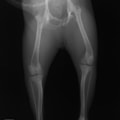

■ 症例20 ポメラニアン 8ヶ月 1.8kg

左右膝蓋骨脱臼 グレードⅢ

2ヶ月前から間欠的跛行が認められ、両膝の膝蓋骨脱臼整復術を行った。

手技は縫工筋及び内側広筋の解放、脛骨粗面の外側転位、滑車ブロック形造溝術、内外側関節包の縫縮を選択し実施した。

右側の膝蓋骨脱臼は上記手技で整復されたものの、左側はそれのみでは膝蓋骨が浮く様子が認められた。その為、PDS縫合糸にて膝蓋靱帯を1糸のみ縫合し、靱帯の縫縮を行った。

膝蓋骨脱臼は膝関節における膝蓋骨の内外側の脱臼と定義されるが、時として単純な内外の脱臼ではなく、膝蓋骨が大きく前方に浮き上がるように脱臼する場合がある。特にトイプードルやポメラニアンといった犬種に多く認められる。

内側脱臼に加えて前方への浮き上がりを矯正する為に、従来より脛骨粗面転移により膝蓋靭帯を外方と下方に引っ張り、固定する方法を選択する。膝蓋骨の前方への浮き上がりが軽度の場合は、従来法ではなく関節包の縫縮で対応していた。しかし、一部の症例で膝蓋骨の動きが悪くなり伸展機構が円滑に機能せずロボット様歩行になるケースがあった。

その為、膝蓋靭帯自体を縫縮する方法を採用した。この方法により、膝関節の伸展機構を妨げず膝蓋骨の軽度の浮きを矯正することが可能となった。

本症例の経過は良好である